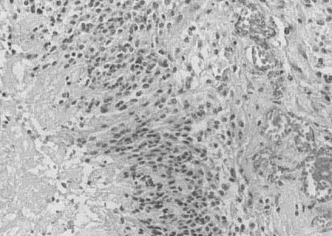

При патологоанатомическом исследовании в случае гибели организма в разгар острой лучевой болезни, вызванной облучением быстрыми нейтронами или гамма-лучами высоких энергий, обращает на себя внимание полнокровие и отек скелетных мышц, а также кровоизлияние, особенно в местах инъекций или механической травмы. При микроскопическом исследовании на первый план тоже выступают полнокровие капилляров и кровеносных сосудов, отек и высокое содержание кислых мукополисахаридов в основном веществе межуточной ткани и стенок кровеносных сосудов.

На этом фоне в мышечных волокнах обнаруживаются волны сокращения, признаки дискоидного и фибриллярного распада, миолиза. В большинстве мышечных волокон отсутствует поперечная исчерченность, выявляется фуксинофнлия и неспецифическая пиронинофилия, свидетельствующая о белковой дегенерации миолазмы, низкая активность цитохромоксидазы и сукцинатдегидрогеназы, небольшое содержание ДНК, РНК и гликогена, повышенная активность щелочной фосфатазы, увеличение свободных липидов и значительное уменьшение фосфолипидов. Определяются и более грубые изменения в виде вакуолизации, глыбчатого распада, наличия крупных капель жира в миоплазме, растворения и распада ядер. Встречается большое количество волокон с неразделившимися ядрами, а также с цепочками гиперхромных мелких ядер, преимущественно в пиронинофильных волокнах.